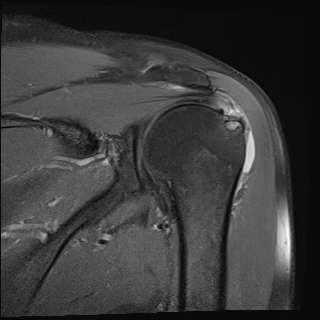

±Ø»ó°Ç ÆÄ¿­, Á¡¾×³¶¿°, °ßºÀÇÏ °ñ±Ø

¹æ»ç¼±»çÁøÀ̳ª ÀÚ±â°ø¸í°Ë»ç¿¡¼­ °ñ±ØÀÌ °üÂûµÇ°í ±Ø»ó°Ç ÆÄ¿­ÀÌ ÀÖ´Â °æ¿ì °Ë»ç¿¡¼­ º¸ÀÌ´Â

°ñ±ØÀÌ ±Ø»ç°ÇÆÄ¿­ÀÇ ¿øÀÎÀ̶ó°í ÃßÁ¤ÇÒ ¼öµµ ÀÖ´Ù.  ±×·¯³ª ±Ø»ó°ÇÆÄ¿­ÀÌ Ç¥Ãþº¸´Ù´Â ½ÉÃþ¿¡¼­

´õ ¸¹ÀÌ ¹ß»ýÇϰí Áõ»óÀ» ÀÏÀ¸Å°Áö ¾Ê´Â °ñ±ØÀÌ ¸¹Àº Á¡À» °í·ÁÇÒ ¶§ °Ë»ç¿¡¼­ º¸ÀÌ´Â °ñ±ØÀ»

Ä¡·á(°ßºÀ¼ºÇü¼ú)ÀÇ ´ë»óÀ¸·Î ÇÏ´Â °ÍÀº Çϸ®ÀûÀÎ °áÁ¤ÀÌ ¾Æ´Ï´Ù. ÀÌ È¯ÀÚÀÇ °æ¿ìó·³ ±Ø»ó°Ç

³»ÃøÀÇ ºÎÁ¾°ú Ç¥Ãþ ¶Ç´Â ÀüÃþ ÆÄ¿­ÀÌ ÀÖÀ¸¸é¼­ Á¡¾×³¶ÀÇ ºÎÁ¾°ú Ãæµ¹°Ë»ç ½Ã Ãæµ¹ ¼Ò°ßÀ» º¸ÀÌ´Â °æ¿ì¿¡

¹æ»ç¼±À̳ª ÀÚ±â°ø¸í°Ë»ç¿¡¼­ º¸ÀÌ´Â °ñ±ØÀÌ ±Ø»ó°Ç ÆÄ¿­ÀÇ ¿øÀÎÀ¸·Î ÃßÁ¤ÇÒ ¼ö ÀÖ´Ù.